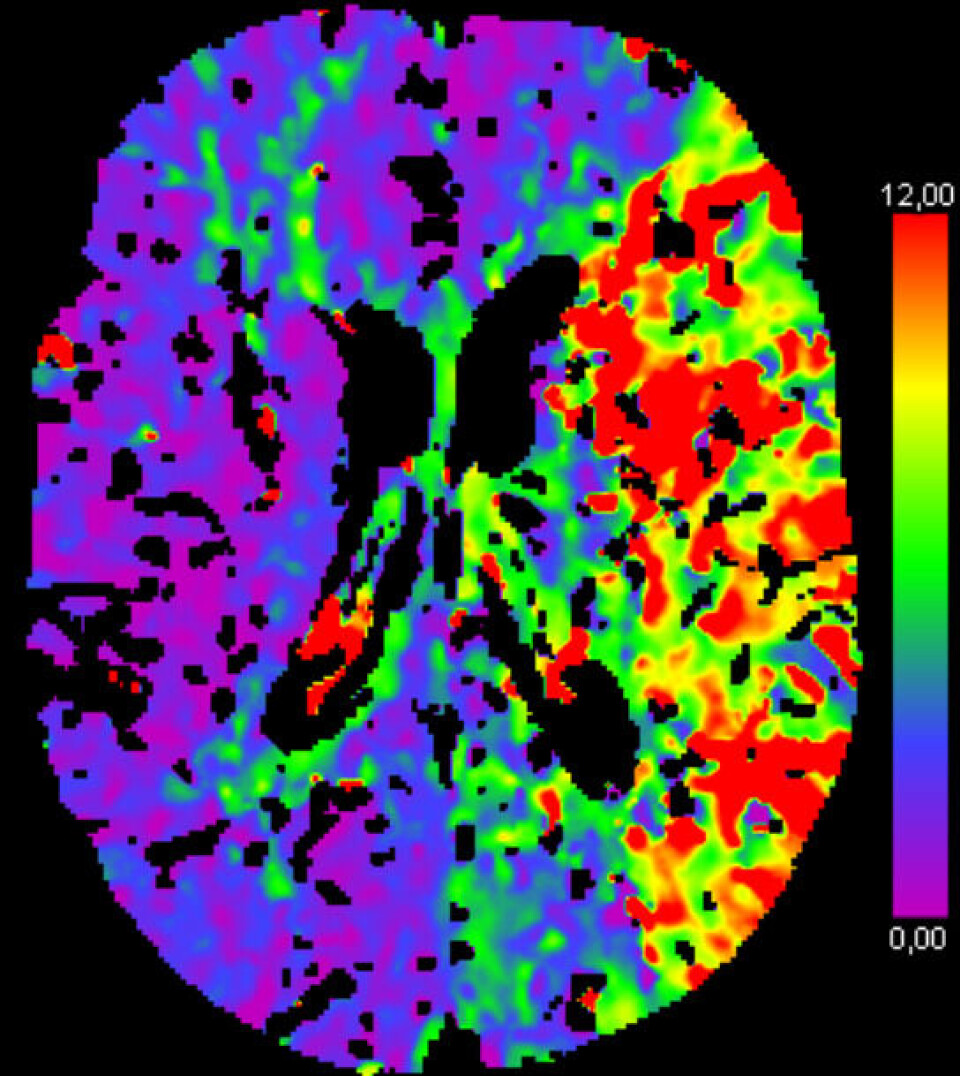

He has used images from CTP (computed tomography perfusion) scanning as input for an artificial intelligence network that can segment the areas of the brain with reduced blood supply.

In other words, identify the areas of the brain that should be treated.

Their research shows that using images based on CT perfusion as input for artificial intelligence increases the possibility of distinguishing the stroke-affected areas.